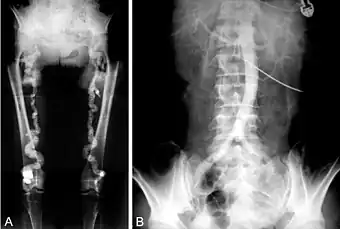

Often Mönckeberg's arteriosclerosis is discovered as an incidental finding in an X-ray radiograph, on mammograms, in autopsy, or in association with investigation of some other disease, such as diabetes mellitus or chronic kidney disease. Typically calcification is observed in the arteries of the upper and lower limb although it has been seen in numerous other medium size arteries.[5] In the radial or ulnar arteries it can cause "pipestem" arteries, which present as a bounding pulse at the end of the calcific zone. It may also result in "pulselessness." Epidemiological studies have used the ratio of ankle to brachial blood pressure (ankle brachial pressure index, ABPI or ABI) as an indicator of arterial calcification with ABPI >1.3 to >1.5 being used as a diagnostic criterion depending on the study.[14][15]

A. Pelvic and lower extremity radiograph shows extensive calcification of the femoral arteries. B. Translumbar aortography shows near-total obstruction of the femoral arteries.